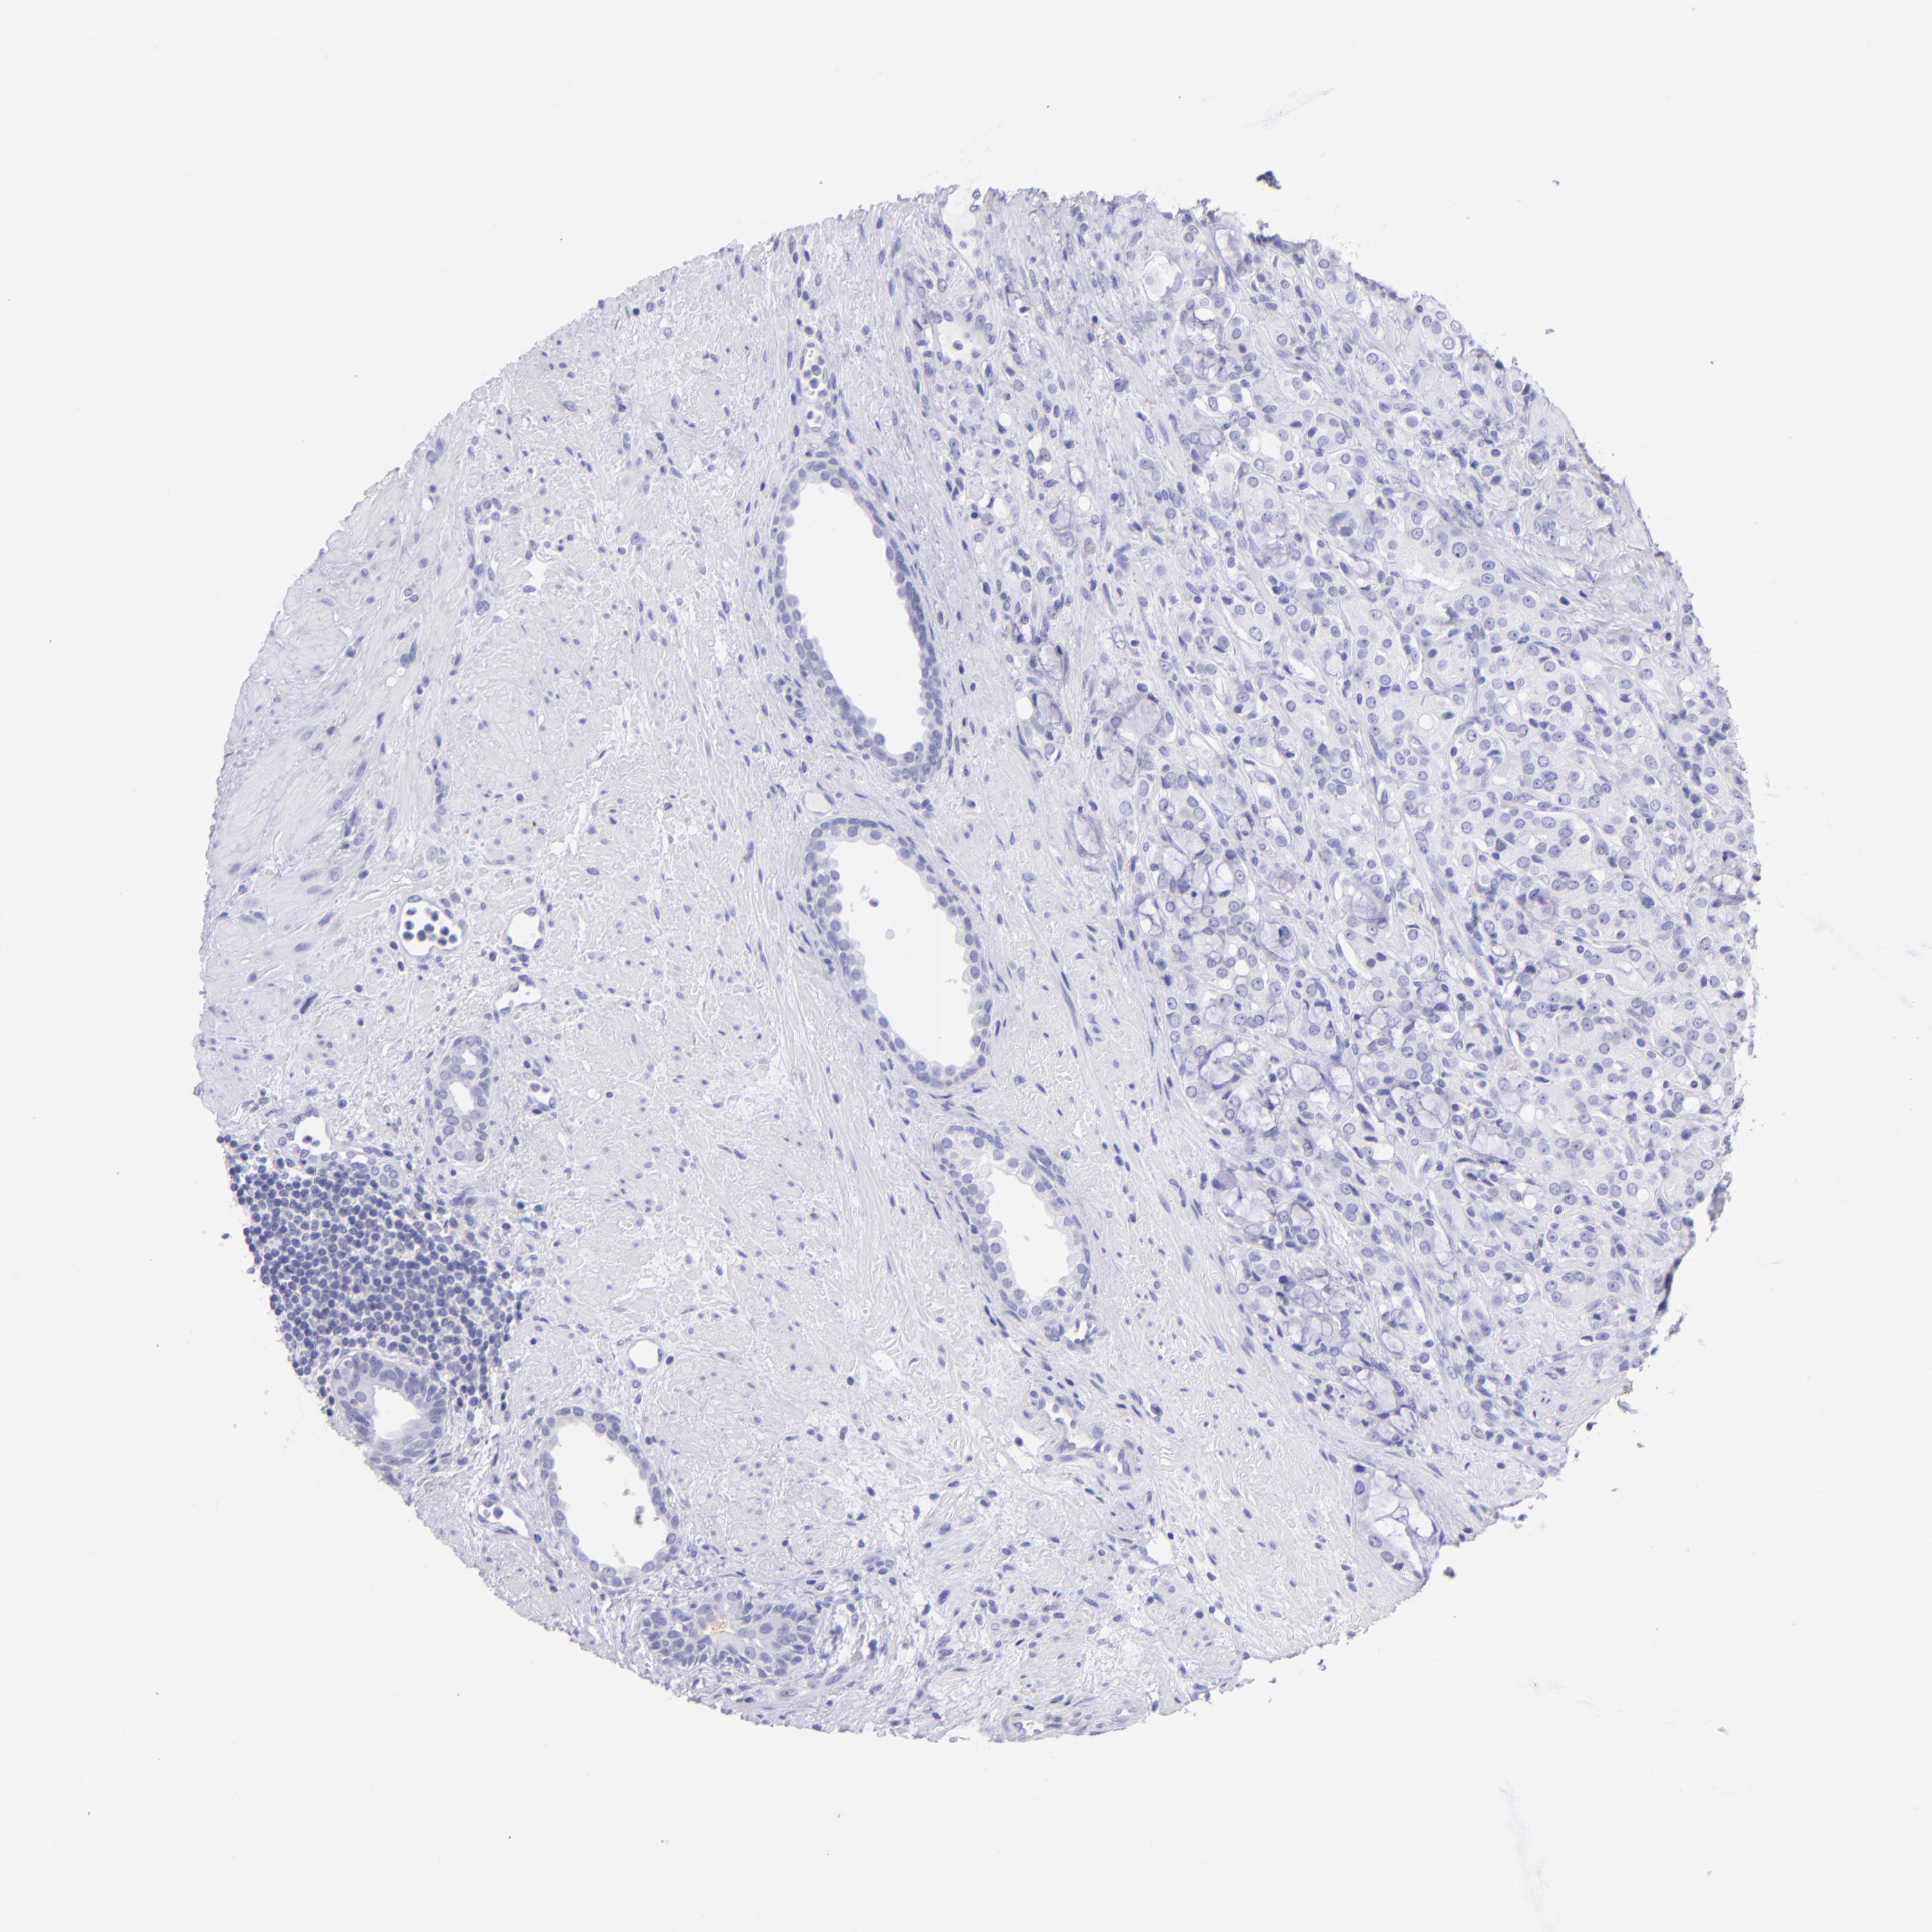

PROSTATE CANCER - Protein expressioni

A mouse-over function shows sample information and annotation data. Click on an image to view it in a full screen mode. Samples can be filtered based on level of antibody staining by selecting one or several of the following categories: high, medium, low and not detected. The assay and annotation is described here.

Note that samples used for immunohistochemistry by the Human Protein Atlas do not correspond to samples in the TCGA dataset.

Antibody stainingi

Antibody staining in the annotated cell types in the current human tissue is reported as not detected, low, medium, or high, based on conventional immunohistochemistry profiling in selected tissues. This score is based on the combination of the staining intensity and fraction of stained cells.

Each image is clickable and will lead to virtual microscopy that enables deeper exploration of all samples and also displays staining intensity scores, fraction scores and subcellular localization as well as patient and tissue information for each sample.

Antibody HPA009177

Antibody CAB002661

Adenocarcinoma, Low grade

Adenocarcinoma, High grade

Adenocarcinoma, Medium grade